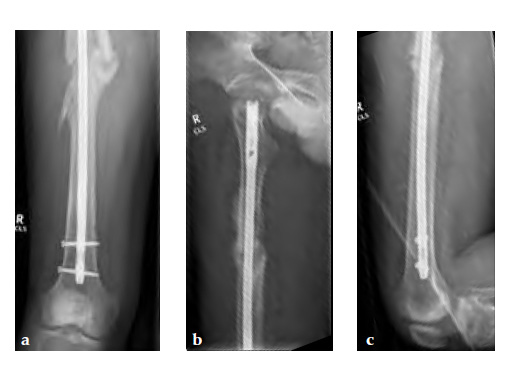

Three weeks prior to her last admission, she complains of recurrent right thigh pain for which epidural analgesics were administered for presumed radiculopathy, however preliminary x-rays and even MRI of the thigh were also taken in view of her primary complaint regarding her right thigh. These investigations did not indicate the possibility of impending bisphosphonate related femur fracture. It is clear from the radiographs that she has an obvious anterolateral bow of her femur and a thickened lateral cortex in the lateral midshaft cortical bone, which may indicate a stress fracture (see Fig 3a-b).

No edema indicated a stress fracture (see Fig 4a-b).

Based on the negative MRI thigh and positive MRI lumbar spine of multiple levels of spinal stenosis, the patient underwent epidural analgesic injection. Patient sustained right femur midshaft periprosthetic fracture the next day after her epidural injection with no trauma.

Notice the fracture decrease the emphasis on the anterolateral bow of the femur (See Fig 5a-b).

Insertion of A2FN as patient may be suffering from a stress fracture related to long term (2.5 years) bisphosphonate use. My rationale against a plate is because bisphosphonate related fractures will heal extremely slowly. In our experience even despite bone grafting union may need up to 2 years. In that time, a plate will fail in less than a year even if the patient is only allowed very minimal weight bearing.